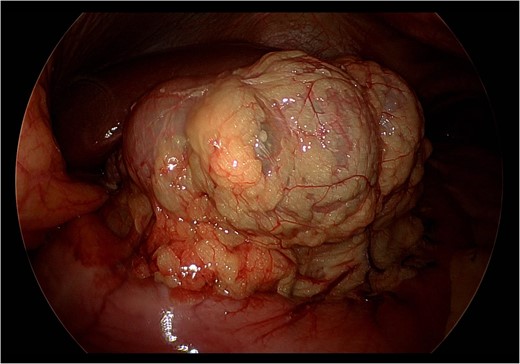

Upon laparoscopic exploration, the cecum was visualized herniating through the foramen of Winslow (Fig. 3), resulting in elevation of the portal structures and biliary compression. The gallbladder was distended with early signs of inflammation. There were no intraabdominal adhesions. Laparoscopic cholecystectomy was executed in standard fashion after obtaining the critical view of safety. Afterwards, using a combination of traction and pushing, the cecum was laparoscopically reduced from the lesser sac (Fig. 4). Although the cecum did not appear ischemic or necrotic, the highly mobile cecum was resected to prevent future volvulus, obstruction, or strangulation. All trocars were then removed, and pneumoperitoneum was released. A small upper midline incision was made, and the cecum and small bowel were extracorporealized. A stapled side-to-side, functional end-to-end, anti-peristaltic ileocolonic anastomosis was performed with 60 mm purple Endo-GIA staplers. With blunt dissection, the foramen of Winslow defect was gently widened to prevent future bowel strangulation. The midline fascia was closed with two running 1 Stratafix sutures. The skin was closed with staples and covered with an incisional negative pressure wound therapy vacuum.

Still photograph obtained during exploratory laparoscopy demonstrating cecal herniation through the foramen of Winslow.